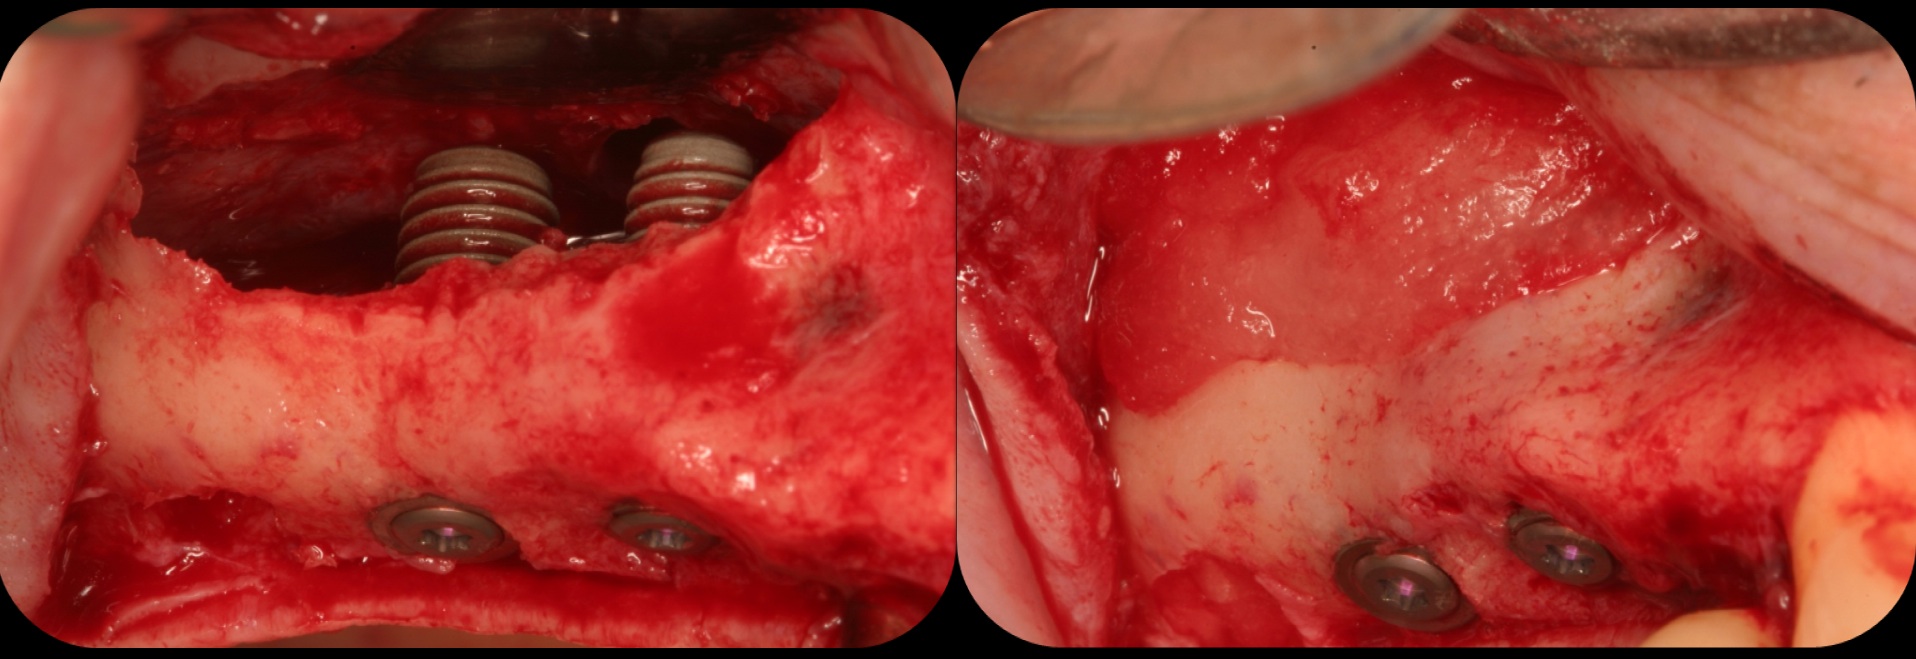

Severe periodontitis lesion.

Fig. 2

Then, too, are opportunities to prepare the site for regeneration by coupling therapies, applying an enamel matrix derivative, along with traditional bone grafts of demineralized freeze-dried bone allograft; potentially, gains in attachment with minimal probing depth and retained papilla may avoid the need for an implant (Figure 2 through Figure 7).